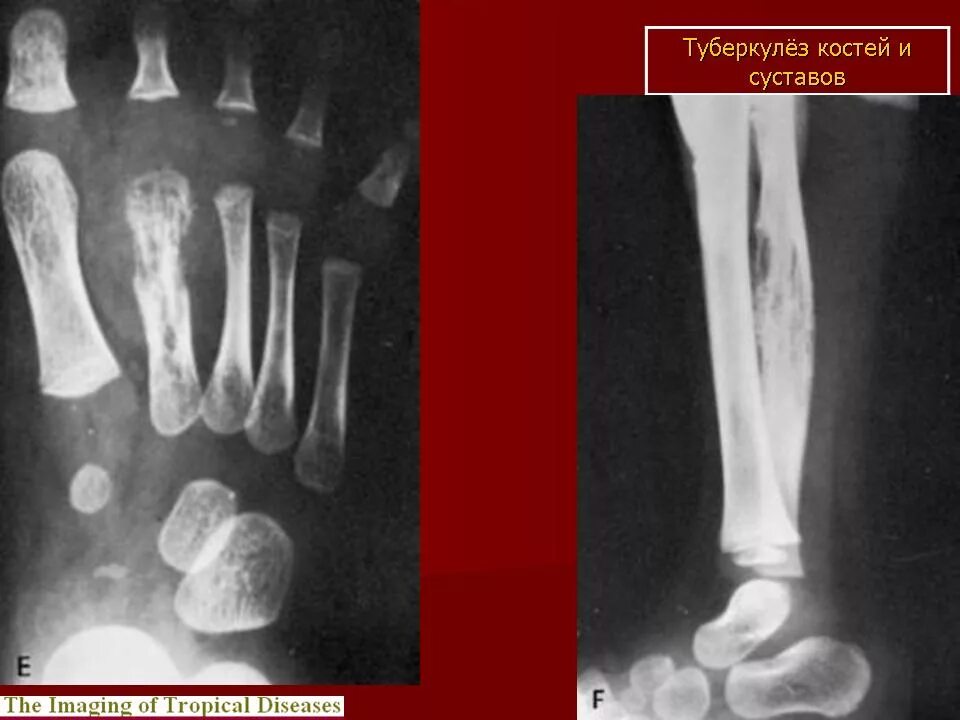

Туберкулез суставов симптомы